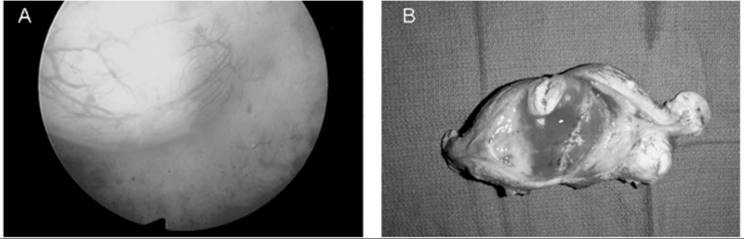

The closer the fibroid is to the endometrial cavity, the greater the likelihood and severity of dysmenorrhea and menorrhagia. Additionally, distortion of the endometrial cavity increases the probability of difficulty in achieving and maintaining a pregnancy. Hysterosalpingography often is undertaken if infertility is present concurrently, because this technique can identify intracavitary tumors or an otherwise normal endometrial cavity enlarged by stretching of the normal myometrium around leiomyomata (Fig. 49.3). This radiographic technique has the added advantage of determining tubal patency. Removal of leiomyomata will not improve the likelihood of conception unless an enlarged endometrial cavity, an irregular endometrial contour, or an intracavitary defect is present. Increasingly, office hysteroscopy is being used when tubal patency is not an issue, because this technique allows clear differentiation between leiomyomata and other intracavitary pathology, such as endometrial adhesions, uterine septae, and endometrial polyps.

FIG. 49.3. An intracavitary leiomyoma. A: A hysterosalpingogram using a water-soluble contrast medium demonstrates a large, smooth filling defect within the endometrial cavity resulting from an intracavitary fibroid. The mass effect on the study is nonspecific, and only direct visualization can confirm that it is caused by a fibroid. B: The hysteroscopic view of this intracavitary leiomyoma.

When clear indications for therapy are present, the most critical questions which must precede a decision are as follows: (a) Is future reproduction is desired? and (b) How soon can menopause be anticipated? Because a simple hysterectomy represents a definitive cure, this is an attractive option for many symptomatic women when maintenance of reproduction is not desired, menopause is not imminent, and more conservative measures have failed to alleviate the symptoms (Fig. 49.4). This also requires an assessment of the woman's individual preferences, as well as her surgical and anesthetic risks. Clearly, women view extirpation of the uterus in their own social, cultural, and religious contexts, and removal of any genital structure cannot be viewed as inconsequential, even if there is no wish to preserve reproductive capacity. As a result, many women wish to preserve the uterus independent of reproduction, and they should be provided with all the therapeutic options and their choices respected. When the preservation of reproductive capacity is desired, a myomectomy is the primary choice. However, because the recurrence risk of symptomatic leiomyomata is high, myomectomy should be viewed as providing a disease-free interval and the women encouraged to attempt to reproduce as soon as is reasonable. As a result, many women without reproductive desires are interested in other, less well-established options such as UAE or myolysis, which may reduce the symptoms and retain the uterus.

FIG. 49.4. Submucous leiomyoma. A: A submucous fibroid visualized at hysteroscopy is from a woman with a history of menometrorrhagia unresponsive to medical management with NSAIDs and oral contraceptives. Although the tumor protrudes into the endometrial cavity, most of it is still within the underlying myometrium. B: The hysterectomy specimen which demonstrates the submucous myoma responsible for the excessive vaginal bleeding.